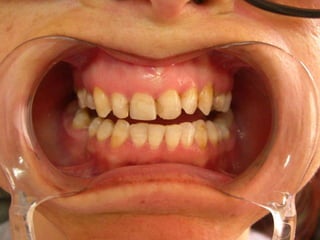

CORONAS DE RECUBRIMIENTO  COMPLETOEstá indicada cuando se necesita máxima protección dental y máxima retención